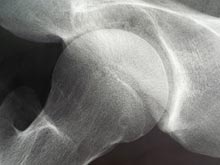

Врачи Госпиталя Бирмингема придумали новую процедуру эндопротезирования тазобедренного сустава. Для имплантата специалисты использовали гипоаллергенный пластик, применяющийся также при изоляции кабелей высокого напряжения, рассказывает DNA India. Новый метод лечения подходит пациентам с суставом, частично пораженным артритом, которым не требуется его полная замена.

Итак, для эндопротезирования используется чаша толщиной 3 миллиметра, изготовленная из поперечно-сшитого полиэтилена. Эта пластмасса признана самой прочной из всех существующих. Как известно, ранее при эндопротезировании применялся сплав кобальта и хрома. У пациентов часто возникали различные по тяжести аллергические реакции на металл. В худшем случае это могло привести к некрозу мышц, окружающих сустав, и потере дееспособности.

Другое преимущество процедуры заключается в том, что удаляется только часть кости. При полной замене бедренного сустава головку бедренной кости меняют на протез. Специалисты считают: поверхностное эндопротезирование бедра особенно показано женщинам. Они чаще страдают аллергией и дисплазией тазобедренного сустава.